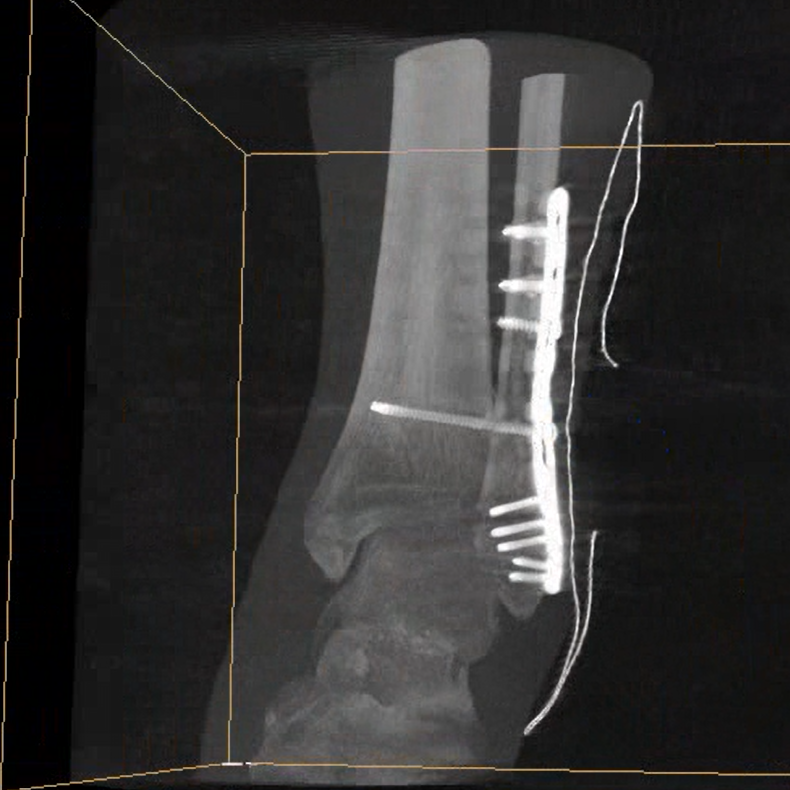

術中三維成像和橫斷面圖像提供多角度的手術診斷信息,輔助醫(yī)生進行術中評估判斷,諸如骨折復位情況和內(nèi)植入螺釘?shù)某叽绾臀恢?,輔助手術更好地完成。